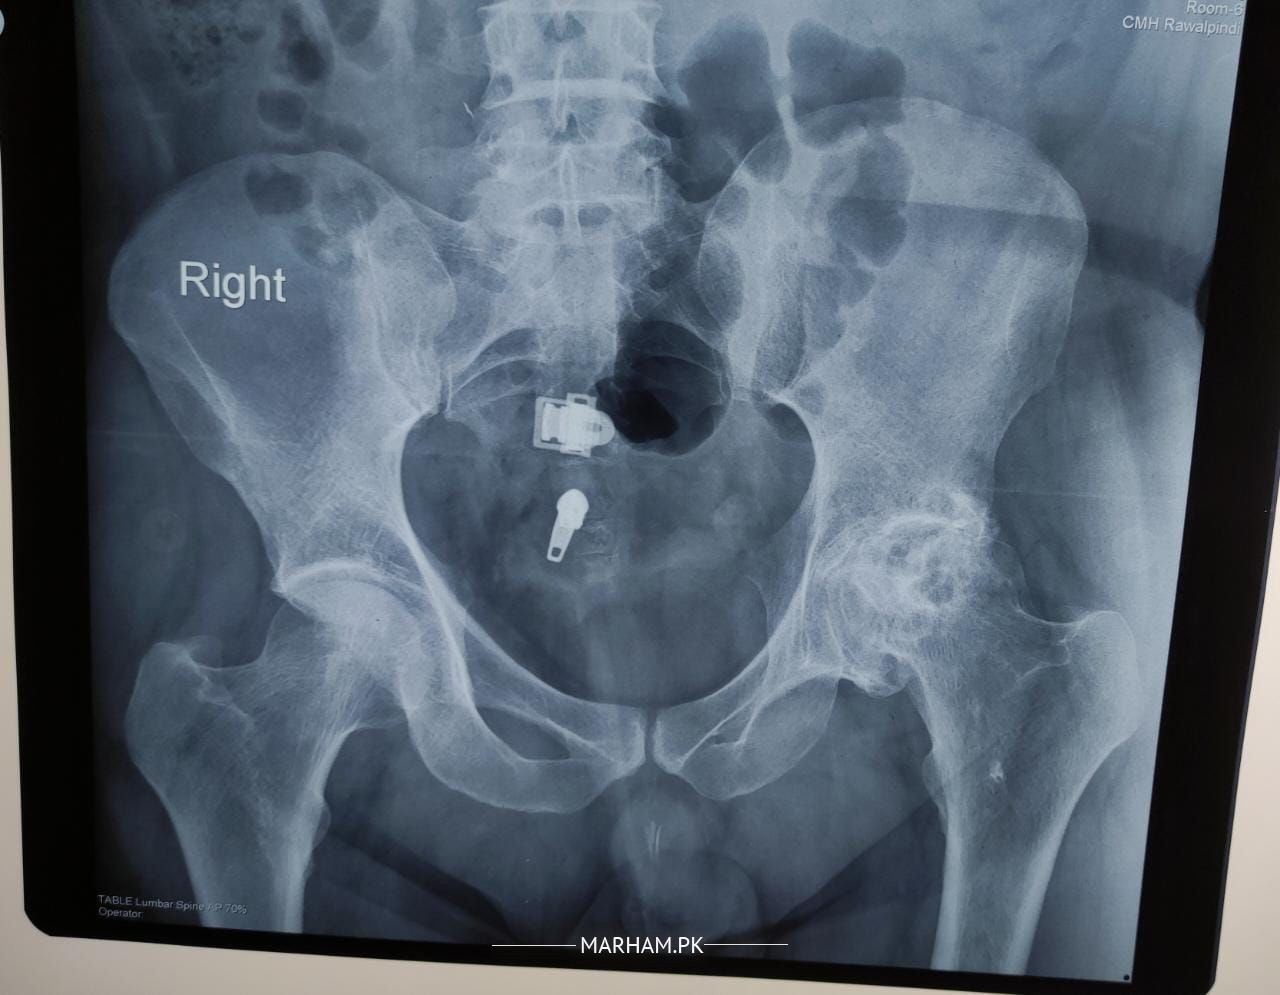

I have attached my X-ray. Surgeon has told me for hip replacement. Is there any other option available

no hip replacement is must needed in ur case

listen to your orthopaedic surgeon

decision must stand with ur surgeon

The options in such cases depends upon:

1- Management of pain with medication

2- Disability affecting daily routine

You are the one to chose. If pain managed on medication and you can manage the disability then no no need. If pain is nor managed by medication and disability is hindering daily routine then please go for surgery. Consult your surgeon for detailed discussion.